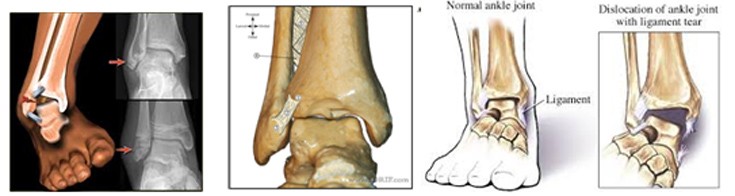

Από τα κατάγματα της ποδοκνημικής, το κάταγμα του έξω σφυρού συνήθως συνοδεύεται από κάταγμα και του έσω σφυρού (αμφισφύριο).

Το κάταγμα του έσω σφυρού συνοδεύεται από ρήξη του δελτοειδούς συνδέσμου.

Αυτό συμβαίνει γιατί τα δύο οστά συγκροτούν μία κολώνα με δύο στηρίγματα. Όταν σπάσει η μία κάπου, πρέπει να σπάσει και η άλλη (καμιά φορά αντί να σπάσει, κόβεται ο δελτοειδής σύνδεσμος ή υφίσταται κάταγμα η κεφαλή της περόνης στο γόνατο (κάταγμα Maisonneuve).

Στα κατάγματα των σφυρών επειδή διαταράσσεται η άρθρωση (υπεξάρθρημα – εξάρθρημα) μετά την κάκωση ο τραυματίας αδυνατεί να πατήσει το πόδι του και να βαδίσει και η άρθρωση φαίνεται πολύ διογκωμένη και παραμορφωμένη.